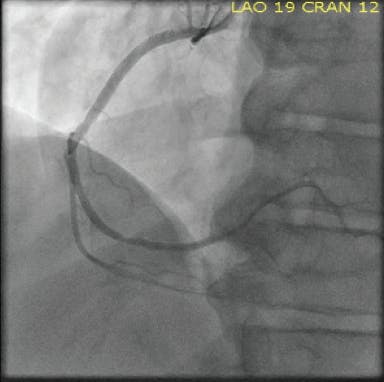

INTERVENTION

An Impella® device (Abiomed, Inc.) was placed emergently on arrival, and perfusion was restored. The initial angiogram showed an occlusion of the proximal left anterior descending (LAD) artery with an acute cutoff, consistent with thrombosis (Figure 1). The lesion was wired with a 0.014-inch balance middleweight wire (BMW; Abbott). CAT RX was used frontline, and flow was restored after two passes with 30 seconds of aspiration (Figure 2). The door-to-device time was 45 minutes. After mechanical thrombectomy, intravascular ultrasound was performed, revealing evidence of plaque rupture and minimal associated plaque burden. Primary stent implantation was therefore performed with a 3- X 28-mm DES, which was postdilated with a 3.25-mm noncompliant balloon to 18 atm. Final angiography revealed TIMI 3 flow with no evidence of distal embolization and restoration of myocardial blush (Figure 3). The Impella® device was removed at the end of the procedure. The patient experienced a full recovery and was discharged from the hospital after 3 days.

Figure 1. Initial angiogram showing occlusion of the proximal LAD.

Figure 2. Flow through LAD after mechanical thrombectomy with CAT RX.

Figure 3. Final angiogram showing TIMI 3 flow through the vessel.